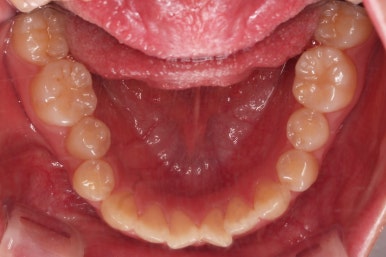

이번 환자분이 선택하신 장치는 눈에 많이 띄는 윗니는 자가결찰 세라믹(데이몬 클리어, Damon clear), 아랫니는 자가결찰 메탈(엠파워 메탈, Empower metal)을 사용했어요.

윗니는 가지런하게 하는 동안 아랫니는 중앙선을 개선하기 위해 미니스크류를 이용해 뒤로, 뒤로 계속 당겨주게 됩니다.

힘 조절도 적절히 해가면서 아래 치열을 뒤로뒤로 옆으로 옆으로 밀어줍니다.

만족스러운 수준까지 정중선을 개선하고 교합도 개선한 뒤, 마무리를 해줍니다.

정중선을 개선하는게 참 오래 걸리는 치료이기는 해서 26개월이라는 부산교정 시간이 걸리긴 했는데요.

교합, 중앙선 등 모든게 많이 좋아진 만족스러운 치료였습니다.